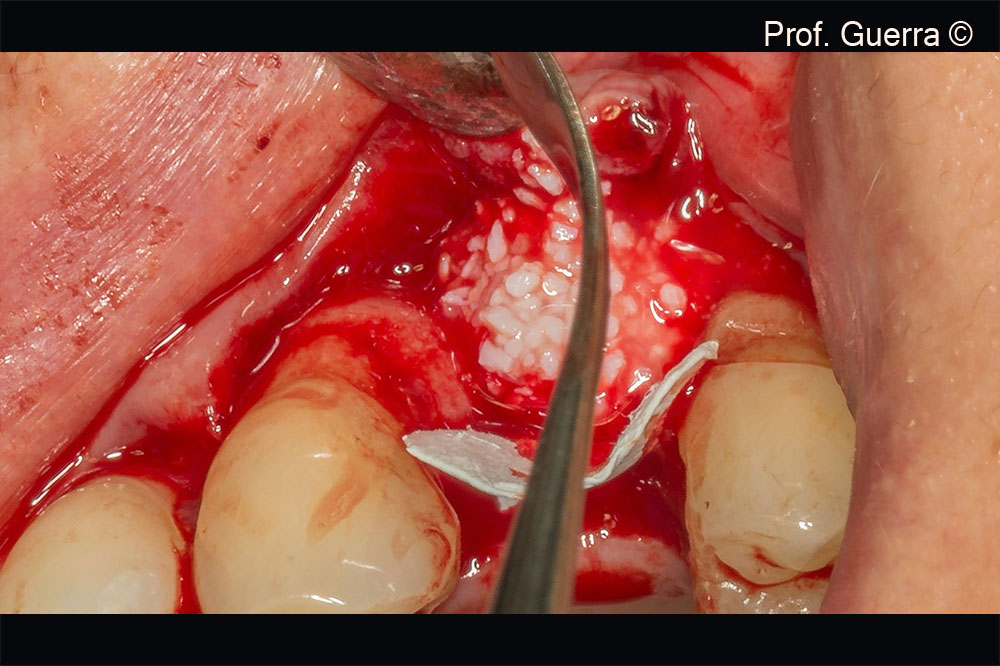

Gen-Os® particles placement

Evolution membrane in place